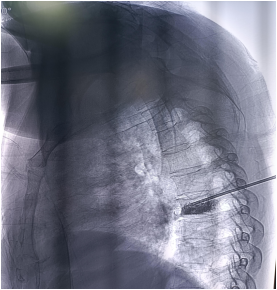

肿瘤转移病损椎体成形术(四)

对于肿瘤导致的椎体压缩性骨折后出现的疼痛,椎体成形术是一种有价值的辅助治疗手段。恶性肿瘤所致的椎体转移性疼痛;存在骨折风险;经核磁共振成像或核素成像证实的有症状的椎体微骨折和(或)CT 提示溶骨性病变且椎体高度无明显变小;骨转移放疗后疼痛不能缓解的患者。

经皮椎体成形术优势:

1.止痛快、疗效佳;

2.创伤小、手术风险低、并发症少,无需缝合;

3.康复快,住院时间短,减少癌痛患者长期卧床引发的并发症;

术后椎体强度和稳定性增强,同时可防止病损骨折椎体的压缩、塌陷。